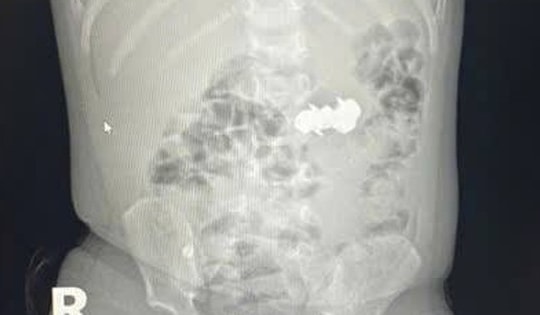

Phẫu thuật kịp thời cứu bé 4 tháng tuổi mắc tim bẩm sinh hiếm gặp

Bệnh viện Sản Nhi Nghệ An vừa phẫu thuật thành công, cứu sống bé gái 4 tháng tuổi mắc dị tật tim bẩm sinh phức tạp, nhập viện trong tình trạng suy hô hấp nặng, tím tái. Sau hơn 20 ngày hồi sức tích cực hậu phẫu, trẻ đã ổn định, đủ điều kiện xuất viện trở về với gia đình.